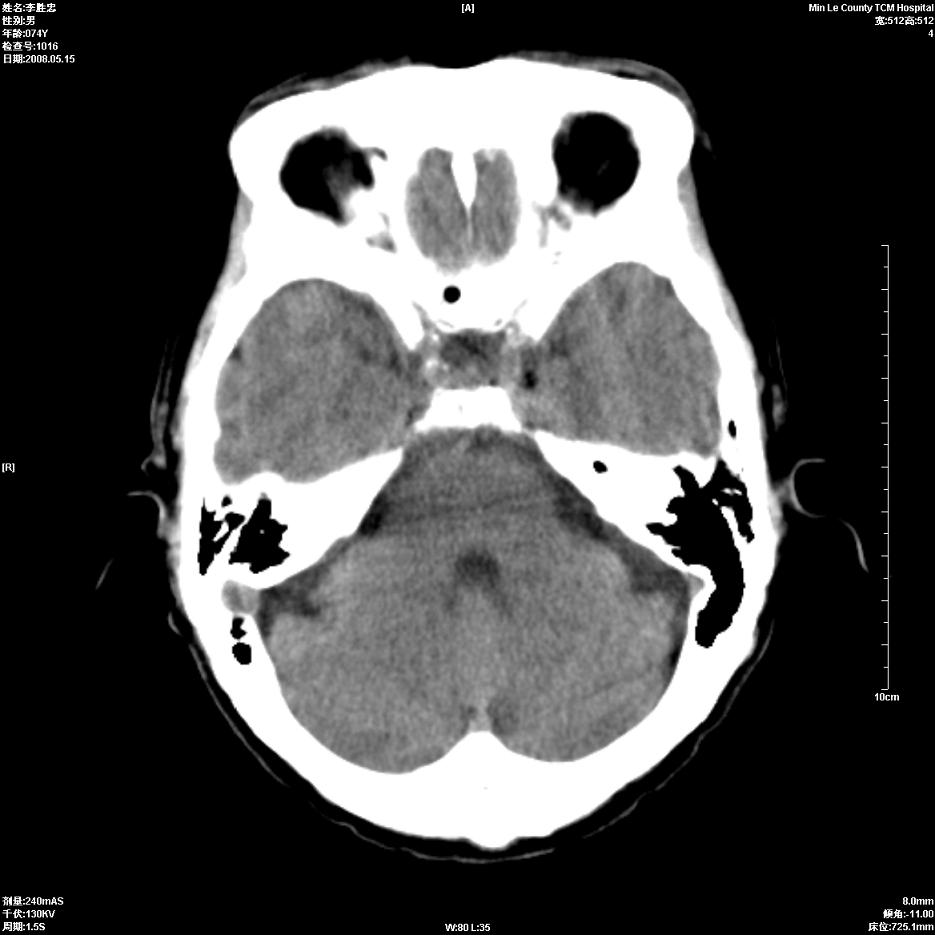

以下是引用hhcckk在2008-5-30 14:26:00的发言:[br]病灶跨中线,有占位效应,强化不明显,考虑胼胝体区低级别的星形细胞瘤可能性大,建议mr检查